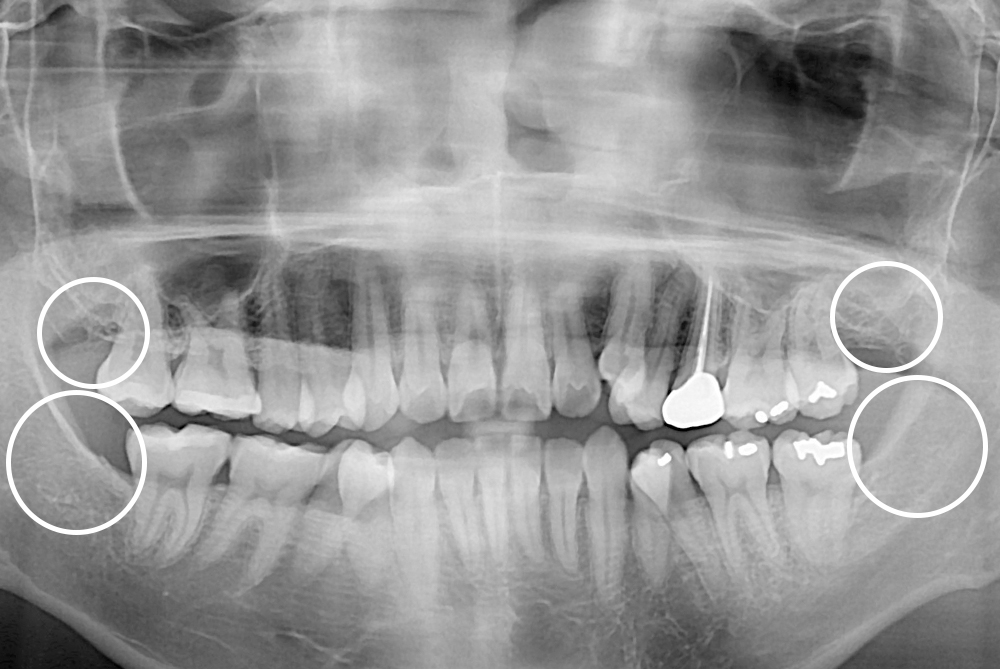

치료후 : 2017-09-11

세종치과는 구강악안면외과학 박사이신 원장님이 발치하는 치과입니다.